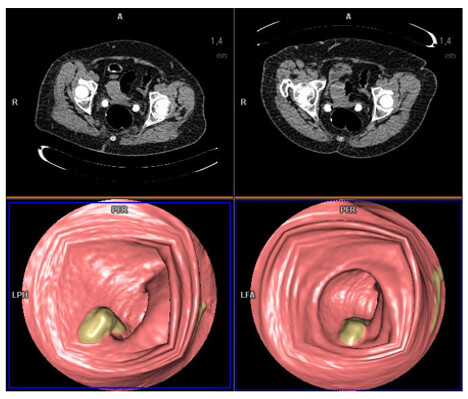

Colonic Endoscopy

The lowest Hounsfield units voxels (near air) have a maximum transparency effect. The voxels with great HU present a significant opacity which materializes the wall of the colon. This is a 3D visualization of the interior of a hollow organ.